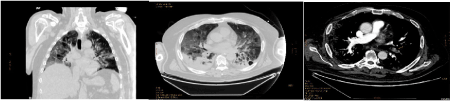

Preliminary examinations of radiological images of full-blown disease showed interstitial pneumonia in 90%. The dominant distribution was along broncho-vascular axis (74%), while subpleural involvement was present in (68%). Mostly, multiple lesions were observed (85%). Their shape was heterogeneous, as well as the density: ground-glass shadow (63%), nodular (25%), grid-like (13%), patchy (11%), crazy-stones-like (4%), honey-comb (4%), lumpy (1%), with interlobular septal thickening in 6%, consolidation in 75%, accompanied by air-bronchograms (10%), bronchiectasis/atelectasis (10%), pleural effusion (39%), pericardial effusion (14%), mediastinal lymphonodes (49%) (Figures 3a and 3b). Honey-comb aspects were observed only in lymphopenic patients, pleural effusion mainly in these ones, air-bronchograms in all non-survivors. Comorbidity with emphysema was present in 40% of non-survivors without lymphopenia, 60% of non-survivors with lymphopenia. Control chest Rx/TC showed clear evidences of worsening in 19/72 (26%), stability in 11/72 (15%), improvement in 36/72 (50%) patients. Nine patients (10%) died, 8/89 (9%) showed clinical improvement and were transferred/discharged before control Rx/TC. In the other patients, new lesions were concomitantly present with aspects of improvement of older ones. Improvement was present in imagings of 15/30 (50%) lymphopenic survivors (group Aa) and 0/16 (0%) non-survivors (Ab), in 19/29 (66%) survivors (group Ba) and 2/9 (22%) non-survivors (Bb), without lymphopenia. Worsening was described in 7/30 (23%) Aa, 9/16 (56%) Ab, 0/29 (0%) Ba, 3/9 (33%) Bb. Peripheral, deep arterial or venous thrombosis was detected in 4/89 (4%), pulmonary thromboembolism in 3/89 (3%) (Figure 3).

Figure 3. Coronal (left) and axial (right) chest CT imagings in a 63 years old, male patient, affected with SARS-CoV2. (C)Thrombo-embolic aspect (arrow) in an axial chest CT imaging with contrast in a 63 years old, male patient, affected with SARS-CoV2